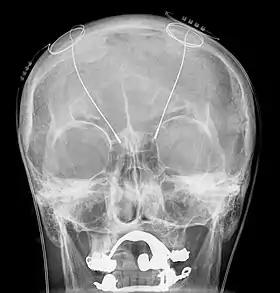

The DBS system consists of three components: the implanted pulse generator (IPG), the lead, and an extension. The IPG is a battery-powered neurostimulator encased in a titanium housing, which sends electrical pulses to the brain that interfere with neural activity at the target site. The lead is a coiled wire insulated in polyurethane with four platinum-iridium electrodes and is placed in one or two different nuclei of the brain. The lead is connected to the IPG by an extension, an insulated wire that runs below the skin, from the head, down the side of the neck, behind the ear, to the IPG, which is placed subcutaneously below the clavicle, or in some cases, the abdomen.[8] The IPG can be calibrated by a neurologist, nurse, or trained technician to optimize symptom suppression and control side effects.[35]

All three components are surgically implanted inside the body. Lead implantation may take place under local anesthesia or under general anesthesia ("asleep DBS"), such as for dystonia. A hole about 14 mm in diameter is drilled in the skull and the probe electrode is inserted stereotactically, using either frame-based or frameless stereotaxis.[37] During the awake procedure with local anesthesia, feedback from the person is used to determine the optimal placement of the permanent electrode. During the asleep procedure, intraoperative MRI guidance is used for direct visualization of brain tissue and device.[38] The installation of the IPG and extension leads occurs under general anesthesia.[39] The right side of the brain is stimulated to address symptoms on the left side of the body and vice versa.